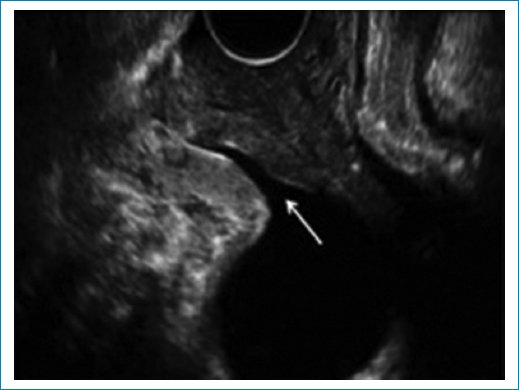

• – Cistocele: con el examen físico solamente podemos evaluar un prolapso de la pared anterior de la vagina; sin embargo, con las imágenes podemos diferenciar entre un cistouretrocele que se asocia a incontinencia de orina y un cistocele con ángulo retrovesical intacto con síntomas de obstrucción al vaciado y baja probabilidad de incontinencia de orina. También puede ser que el prolapso de la vagina anterior sea por un divertículo uretral, quiste de Gartner o un enterocele anterior. El punto de corte para determinar el descenso de la vejiga es 10 mm por debajo de la línea pubiana que se traza perpendicular a la sínfisis pubiana3 (Fig. 7).

Figura 7. Se observa un descenso de la pared posterior vesical por debajo de la línea pubiana, con ángulo retrovesical cerrado.